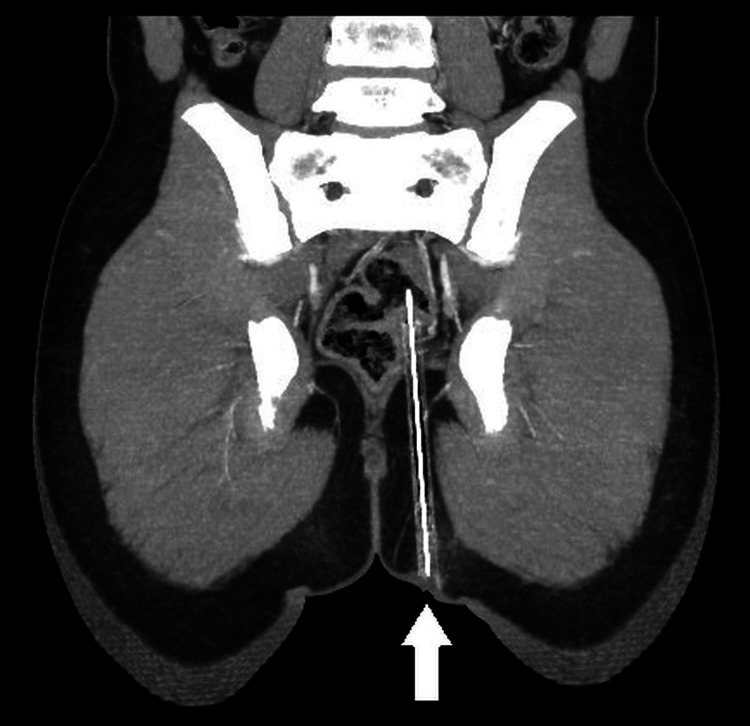

Pensel termasuk ke dalam gluteal sejauh 12.4cm

Walaupun nampak seperti tidak kritikal secara luaran, sebenarnya objek berkenaan telah menembusi daging punggung (gluteal) murid berkenaan sedalam 12.4cm. Imbasan seterusnya turut mengesahkan hujung pensel terbabit sudah terkena pada bahagian rektum (bahagian akhir usus besar).